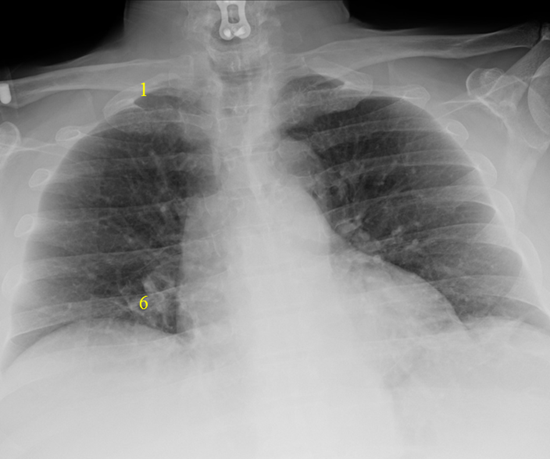

PA Projection – Normal Mediastinum and Good Inspiratory Effort

AP projection is obtained with the patient in bed and lying flat or partly upright. It is usually reserved for non-ambulatory patients. AP projections have the disadvantage of making the heart an mediastinum appear more prominent as well as usually resulting in shallower inspiration which can limit evaluation of the lung bases. A lateral projection is not obtained with a AP projection, thereby limiting the view of the chest further.

AP Projection – Widened Mediastinum and Less Inspiratory Effort

It is therefore preferable to order a PA/lateral CXR over an AP view when possible.